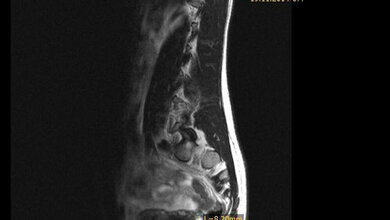

Gutartige Gewebeknoten in der Gebärmutter gehen oft mit Schmerzen oder Krämpfen und verstärkten Monatsblutungen einher. Sie werden herkömmlich durch Arterienembolisation oder durch operative Entfernung der Myome (Myomektomie) oder der Gebärmutter (Hysterektomie) behandelt. Sie können aber auch durch einen genau auf das jeweilige Myom fokussierten Ultraschallimpuls erhitzt und so zerstört werden. Dabei wird die Fokussierung durch Magnetresonanztomographie überwacht.

Diese neue Methode hat im Vergleich zu anderen Interventionen das Potenzial, die Krankenhausverweildauer zu verringern und die Rückkehr zu normalen Aktivitäten zu beschleunigen. Eine Erprobungsstudie zur Gewinnung der notwendigen Erkenntnisse für eine Nutzenbewertung ist laut IQWiG möglich.